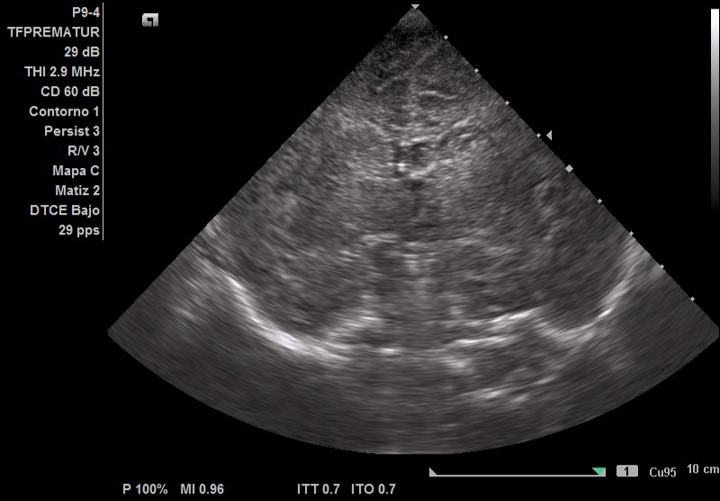

En el corte coronal de la primera ecografía cerebral ( Figura 1B) difícilmente se aprecia un área hiperintensa en territorio de la arteria cerebral media derecha en cambio en la ecografía cerebral realizada a los 4 días se aprecia claramente ( Figura 1C) debido al aumento de la sensibilidad diagnóstica de lesiones isquémicas que ofrece la ecografía a medida que pasan los días. Por ello es importante realizar ecografías secuenciales ante la sospecha clínica de infarto cerebral arterial neonatal.